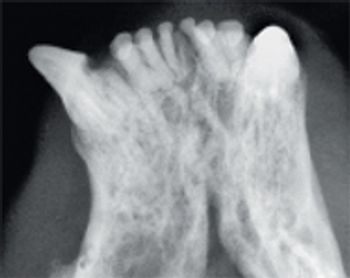

According to industry estimates, less than 10 percent of small animal practices have dental radiograph units and of those, less than 10 percent take intraoral films on every dental case.